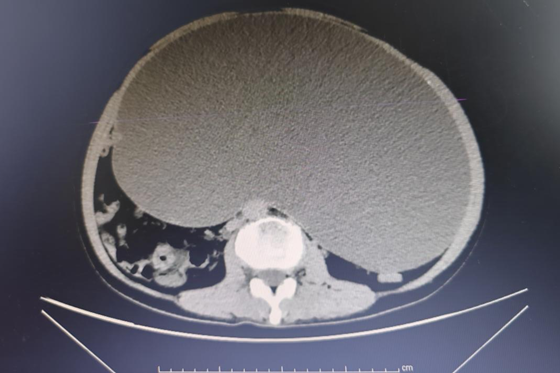

术前CT

入院后, 刘女士进一步完善相关检查,CT增强显示:刘女士盆腹腔内见一个椭圆形低密度灶,大小约为255mm*149mm,考虑为:巨大卵巢粘液性囊腺瘤且右侧输尿管受压,需要手术切除。为确保手术安全,梁丽凌教授带领全科团队进行病例讨论,针对患者病情制定详细的手术方案。